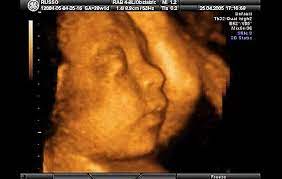

27 hafta gebelik bebek kilosu

27 hafta gebelik bebek kilosu.